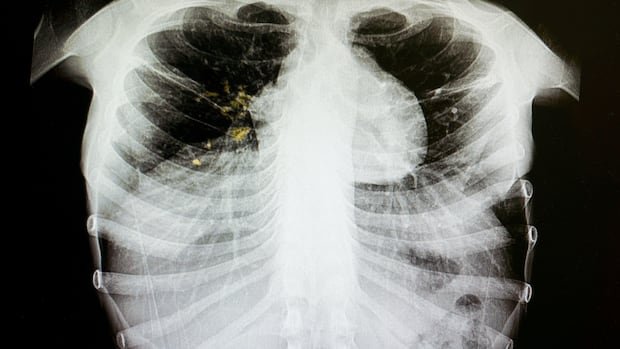

According to PCA, the lab results indicated a recent local transmission of the infectious disease, which primarily affects the lungs but can also impact other body parts. The agency, responsible for primary health services in the province, has identified a total of 12 tuberculosis cases this year related to central Edmonton and individuals experiencing homelessness. Among these cases, three individuals with the same strain are considered part of the outbreak.